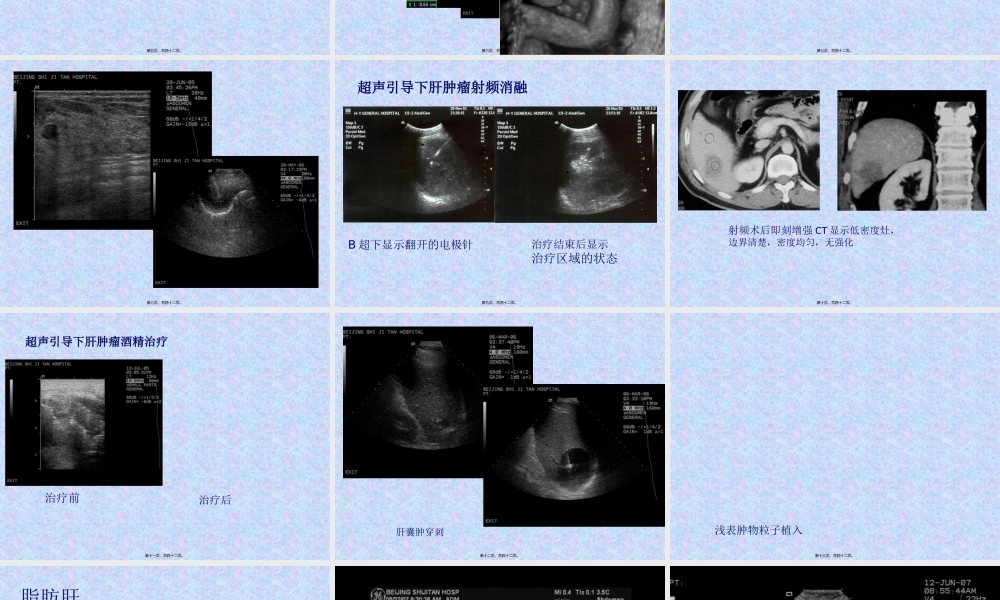

2、本站所有内容均由合作方或网友上传,本站不对文档的完整性、权威性及其观点立场正确性做任何保证或承诺!文档内容仅供研究参考,付费前请自行鉴别。

3、如文档内容存在违规,或者侵犯商业秘密、侵犯著作权等,请点击“违规举报”。

碎片内容